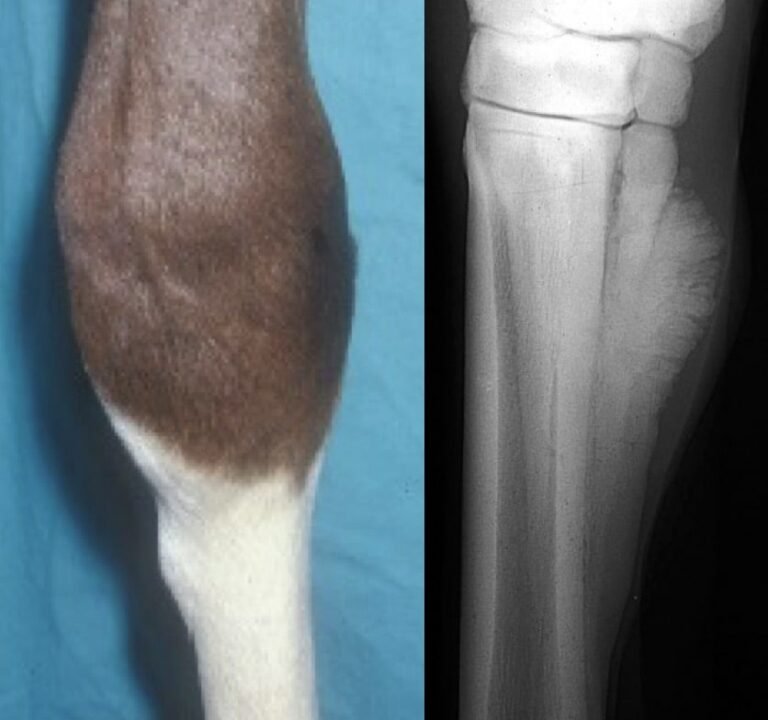

Metacarpal or metatarsal exostosis Etiology and Treatment Shin Splints Horses Treatment The goal in treating splints is to reduce or eliminate the cause of the splint and reduce the inflammation to minimize the amount of boney. Treatment for splints in horses. Best treatment for splints in horses. Treatment typically includes rest, cryotherapy (ice/cold hosing), and supportive wraps. Combined with targeted rehabilitation exercises, these advanced modalities offer promising outcomes for horses battling. Shin Splints Horses Treatment.